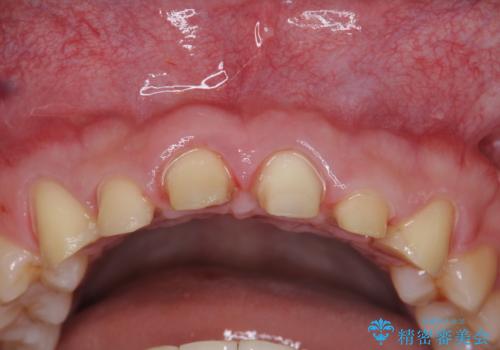

- 「前歯の見た目、歯ぐきの腫れを改善したい。」と希望され来院されました。

前歯には接着性の維持装置や、中途半端な形の連結クラウンが装着され、清掃性が悪く歯ぐきの腫れや、歯ぐきの形態の不揃いが認められました。

ただ、白いオールセラミッククラウンを製作・装着するのではなく、将来にわたり安定した状況を獲得するため、歯周外科を行い歯ぐきと周囲の歯槽骨の形態を整えていきます。

歯周外科を行ったことで、歯ぐきの形態や腫れが改善され、審美性だけでなく清掃性も大きく改善することができました。